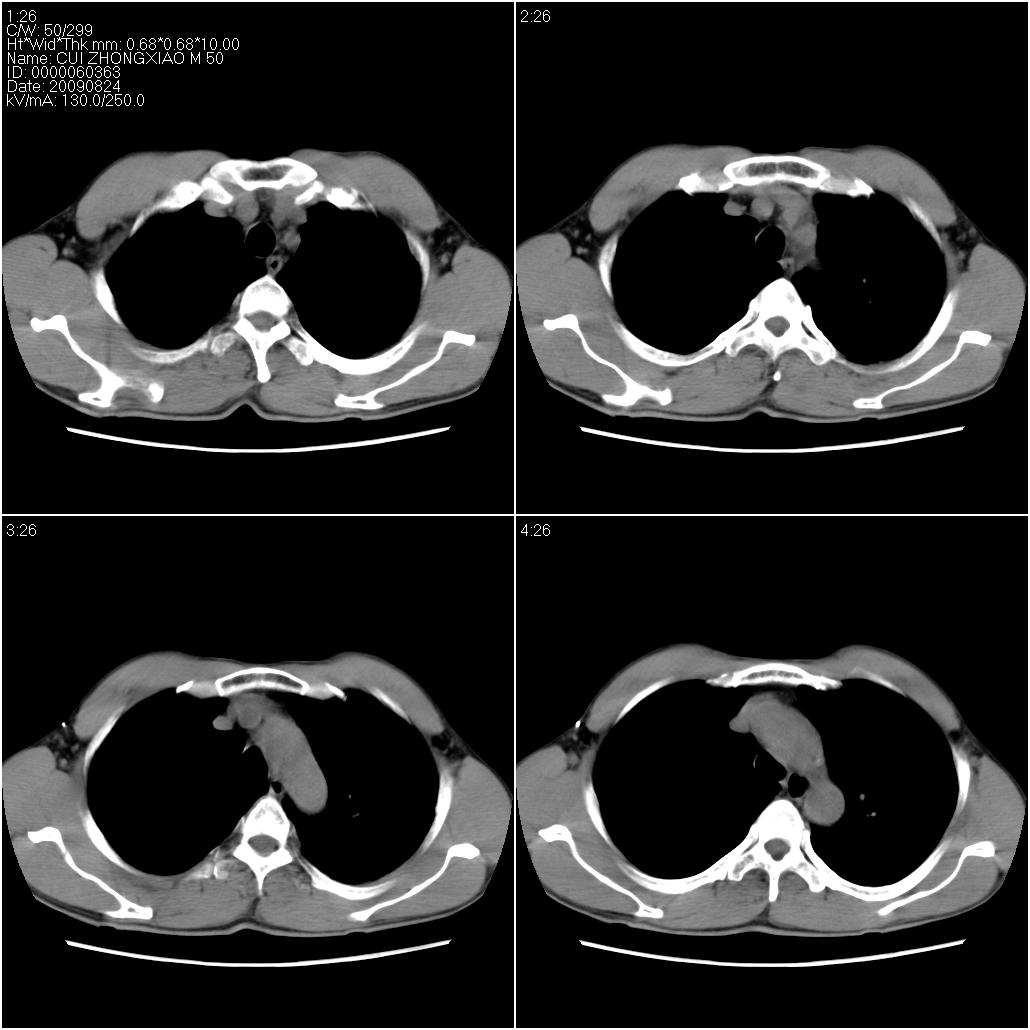

标题: CT21851:男性,50岁。间断性咳嗽半年。 [打印本页]

标题: CT21851:男性,50岁。间断性咳嗽半年。

磨玻璃样改变(左肺及右肺上叶前段),边缘模糊,考虑炎症,建议严格抗炎治疗后复查除外肺泡蛋白沉积症或肺泡出血(病人有咯血吗) 肺泡癌.

肝左叶肝内胆管扩张,进一步检查.